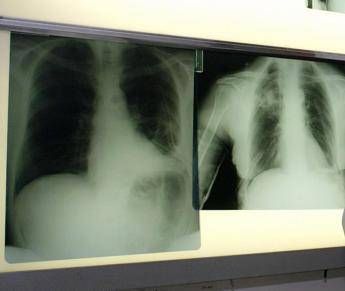

(Adnkronos) – Ogni anno circa 290mila casi di infezione respiratoria acuta negli adulti e 1.800 decessi. Sono i numeri registrati solo in Italia per il virus respiratorio sinciziale (Vrs o Rsv nella sigla inglese), che si presenta con sintomi simil-influenzali, ma può determinare complicanze respiratorie significative nei soggetti fragili come over 60, persone immunocompromesse e neonati. Un fenomeno sottovalutato e sottostimato, specialmente nella popolazione adulta e anziana: spesso, infatti, la malattia da Rsv non viene diagnosticata correttamente. La protezione dei soggetti fragili resta la priorità: in Italia si registrano infatti oltre 50mila ricoveri all'anno. Nel dettaglio si calcano circa 25mila ospedalizzazioni di bambini sotto i 5 anni di età legate alle complicanze come bronchiolite e polmoniti, e circa 26mila negli over 60. Sul fronte della prevenzione, sono oggi disponibili strumenti sicuri ed efficaci come la vaccinazione e l'immunoprofilassi; nonostante queste opportunità, però, l'Rsv non è ancora incluso nel Piano nazionale di prevenzione vaccinale (Pnpv). Di questi temi e della necessità di una informazione corretta e aggiornata sui rischi e sulle strategie di prevenzione a disposizione si è parlato al media tutorial 'Giornalismo scientifico e comunicazione biomedica: il caso della malattia infettiva da virus respiratorio sinciziale' promosso dal Master Sgp – La Scienza nella pratica giornalistica della Sapienza Università di Roma, con il contributo non condizionante di Pfizer, che oggi nella Capitale ha messo a confronto i giornalisti con gli esponenti del mondo medico-scientifico, specialisti in igiene, medicina preventiva e pediatria. La rilevanza per la salute pubblica dei virus respiratori risiede sia nell'impatto socio-sanitario legato alla loro larga diffusione, sia al potenziale pandemico espresso da alcuni ceppi di virus influenzali e coronavirus, ricorda una nota. "La maggior parte dei virus respiratori ha una spiccata tendenza stagionale – afferma Pier Luigi Lopalco, professore ordinario di Igiene, università del Salento – Nell'emisfero Nord del pianeta è nei mesi invernali che si verificano i picchi di infezioni da influenza, virus respiratorio sinciziale, Sars-CoV-2, metapneumovirus, rhinovirus e adenovirus, per citare i più frequentemente diagnosticati. La circolazione combinata di questi virus rende la stagione invernale particolarmente critica in termini di pressione sul sistema sanitario. Ancora oggi le informazioni che abbiamo sulla circolazione dei virus respiratori sono affette da una forte sottostima". Il sistema di sorveglianza, osserva Lopalco, "non è completamente efficiente nel rilevare i casi reali e ciò non consente di valutarne il reale impatto sociosanitario: a questo scopo – suggerisce l'esperto – sarebbe necessario impostare studi ad hoc che, laddove eseguiti, hanno mostrato che il danno individuale e sociale di queste infezioni va ben oltre il periodo della malattia acuta. Nei soggetti fragili e anziani, ad esempio, un periodo di ricovero dopo un'infezione respiratoria può scatenare una serie di complicanze e si associa spesso a una perdita consistente dell'autonomia". In Italia, dopo l'esperienza della pandemia da Covid-19, il sistema di sorveglianza dell'influenza Influnet si è ampliato diventando RespiVirNet, con l'obiettivo di migliorare le conoscenze su altri virus respiratori come l'Rsv che si possono prevenire con la vaccinazione. "La sorveglianza consente di misurare il reale carico di malattia, supporta la programmazione sanitaria e l'allocazione delle risorse, guida le decisioni sulle strategie preventive e aumenta la consapevolezza del carico di malattia – evidenzia Caterina Rizzo, professoressa ordinaria di Igiene e medicina preventiva, università di Pisa – Comprendere e comunicare il peso dell'Rsv a tutti gli attori coinvolti è essenziale per rafforzare la prevenzione, ridurre la sottostima e tutelare le fasce più vulnerabili della popolazione". Il virus respiratorio sinciziale colpisce in modo diverso nelle differenti fasce d'età. L'Rsv "è un virus ubiquitario che colpisce praticamente tutti i bambini entro i 2 anni di vita, con possibili reinfezioni nel corso della prima infanzia e financo in età adulta – illustra Paolo Manzoni, professore associato di Pediatria e neonatologia, università di Torino – Se nei soggetti oltre i 2 anni di età il virus causa spesso sintomi simil-influenzali, colpendo per lo più le vie aeree superiori, al contrario una percentuale importante di pazienti con età meno di 2 anni presenta coinvolgimento delle basse vie aeree che può sfociare, nello specifico, nel quadro clinico classico conosciuto come bronchiolite e nelle sue complicanze sia immediate, sia a lungo termine". Oltre ai neonati prematuri e di età inferiore ai 6 mesi, le popolazioni a rischio di sviluppare una patologia respiratoria grave a seguito di Rsv sono le persone over 60 e quelle immunocompromesse o con patologie preesistenti come il diabete, le malattie cardiache e polmonari, nelle quali il virus può scendere alle vie respiratorie inferiori causando principalmente polmonite. A partire dal 2023 – prosegue la nota – nell'Unione europea sono stati resi disponibili vaccini contro l'Rsv indicati per proteggere sia i neonati fino ai 6 mesi, attraverso la vaccinazione della mamma (le donne in gravidanza possono vaccinarsi dalla 24esima alla 36esima settimana di gestazione), sia adulti e anziani (le società scientifiche raccomandano la vaccinazione per i soggetti a rischio di 60-74 anni e per le persone di età pari o superiore a 75 anni). L'efficacia della prevenzione nelle persone over 60 è stata evidenziata da diversi studi, tra cui una recente esperienza real world pubblicata sul 'New England Journal of Medicine', che ha valutato un primo impatto del vaccino nel prevenire i ricoveri: il bivalente ha ridotto da 0,66 a 0,11 gli eventi per mille persone/anno, con un'efficacia dell'83,3% (Ci 42,9-96,9). Per le forme più gravi (tratto respiratorio inferiore), l'efficacia è salita al 91,7%, superando ampiamente il criterio di successo prespecificato. "Numerosi Paesi hanno già emanato raccomandazioni per la vaccinazione contro l'Rsv in base all'età (≥60, 65 o 75 anni) o ai fattori di rischio. Anche molte società scientifiche hanno fortemente raccomandato questa vaccinazione – rimarca Sara Boccalini, professoressa associata di Igiene, università degli Studi di Firenze – In Italia il Board del Calendario vaccinale per la vita raccomanda l'uso del vaccino contro l'Rsv per tutti i soggetti di età superiore-uguale ai 75 anni e per i soggetti affetti da patologie croniche di età uguale o superiore ai 60 anni. Tuttavia – precisa – al momento la vaccinazione contro l'Rsv non è raccomandata in base all'attuale Pnpv 2023-2025. La speranza è che le istituzioni sanitarie italiane integrino quanto prima l'offerta del vaccino Rsv per la popolazione anziana e a soggetti a rischio per patologie nel calendario delle immunizzazioni offerte attivamente e gratuitamente alla popolazione". La sfida principale – concludono gli esperti – resta duplice: da un lato rafforzare la raccolta di dati epidemiologici solidi per comprendere con precisione la diffusione e l'impatto della malattia infettiva da virus respiratorio sinciziale; dall'altro integrare in modo equilibrato le strategie di prevenzione disponibili, tenendo conto di tutte le popolazioni fragili a rischio di complicanze. Un approccio basato sulle evidenze scientifiche potrà fornire un contributo concreto al dibattito pubblico e istituzionale, sostenendo scelte consapevoli e mirate nella tutela della salute collettiva.